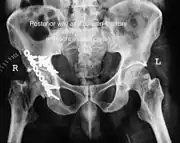

X-ray of T shape fracture

T shape fracture shown on bone model